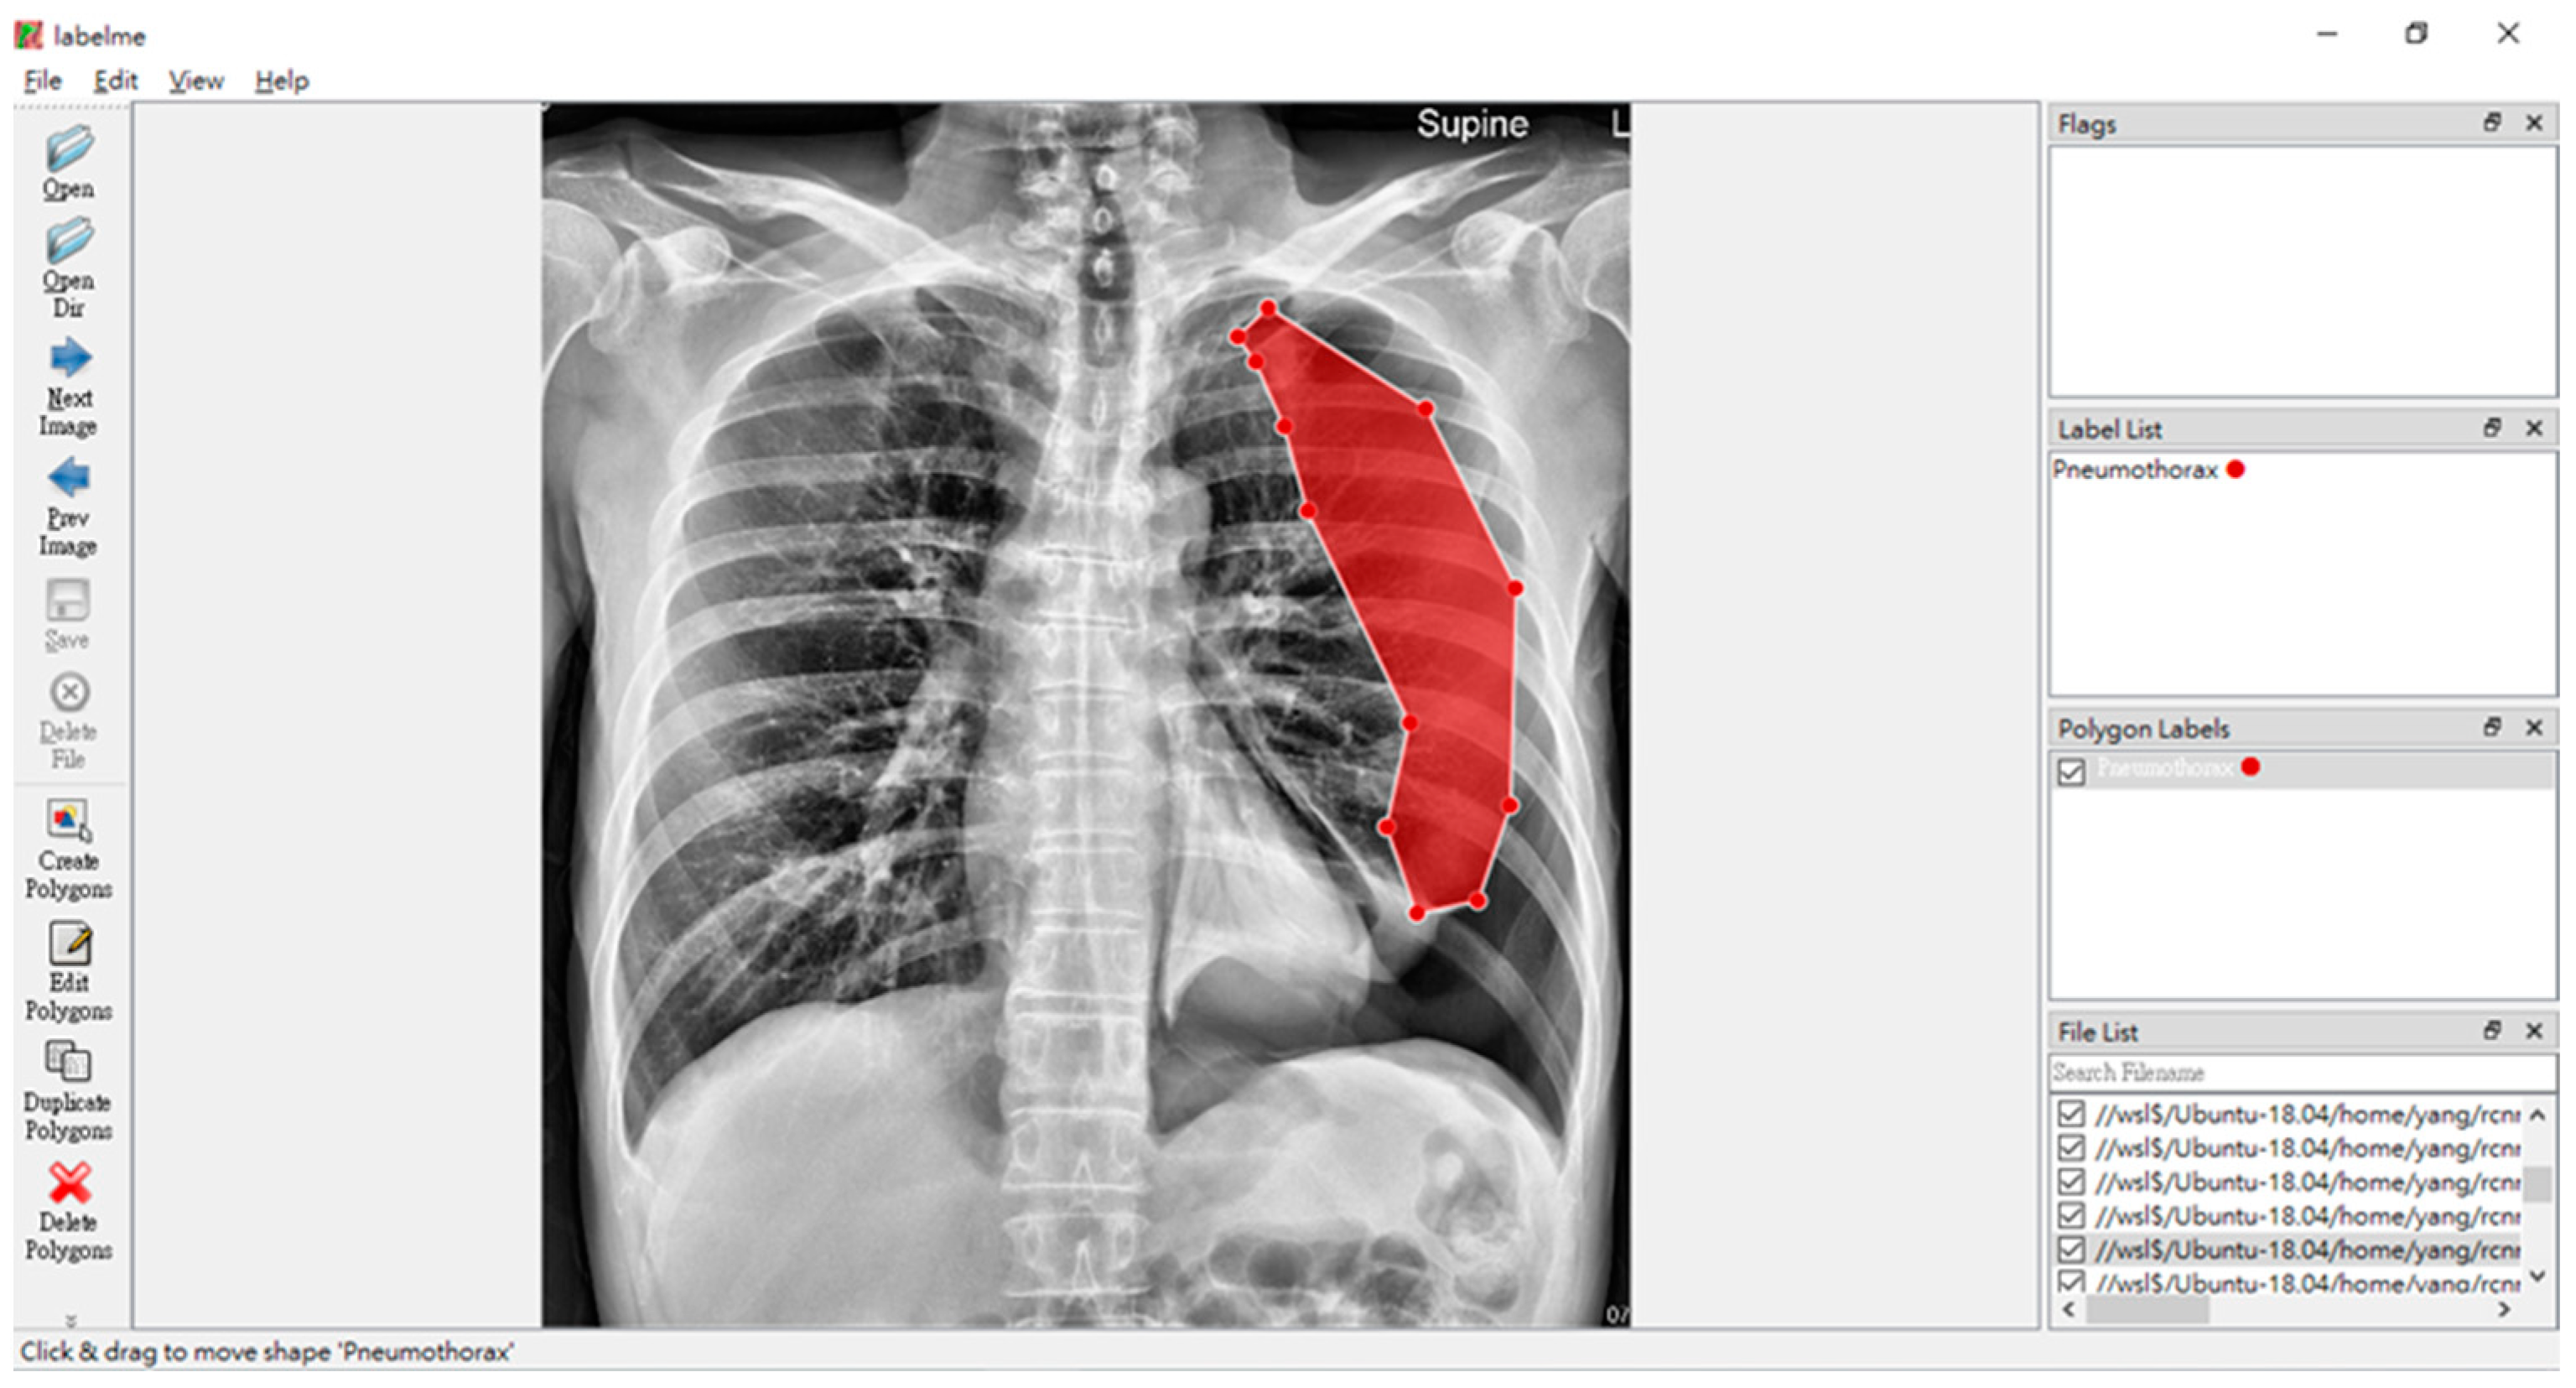

- Russell, B.; Torralba, A.; Murphy, K.; Freeman, W. LabelMe: A Database and Web-Based Tool for Image Annotation. Int. J. Comput. Vis. 2008, 77, 157–173. [Google Scholar] [CrossRef]